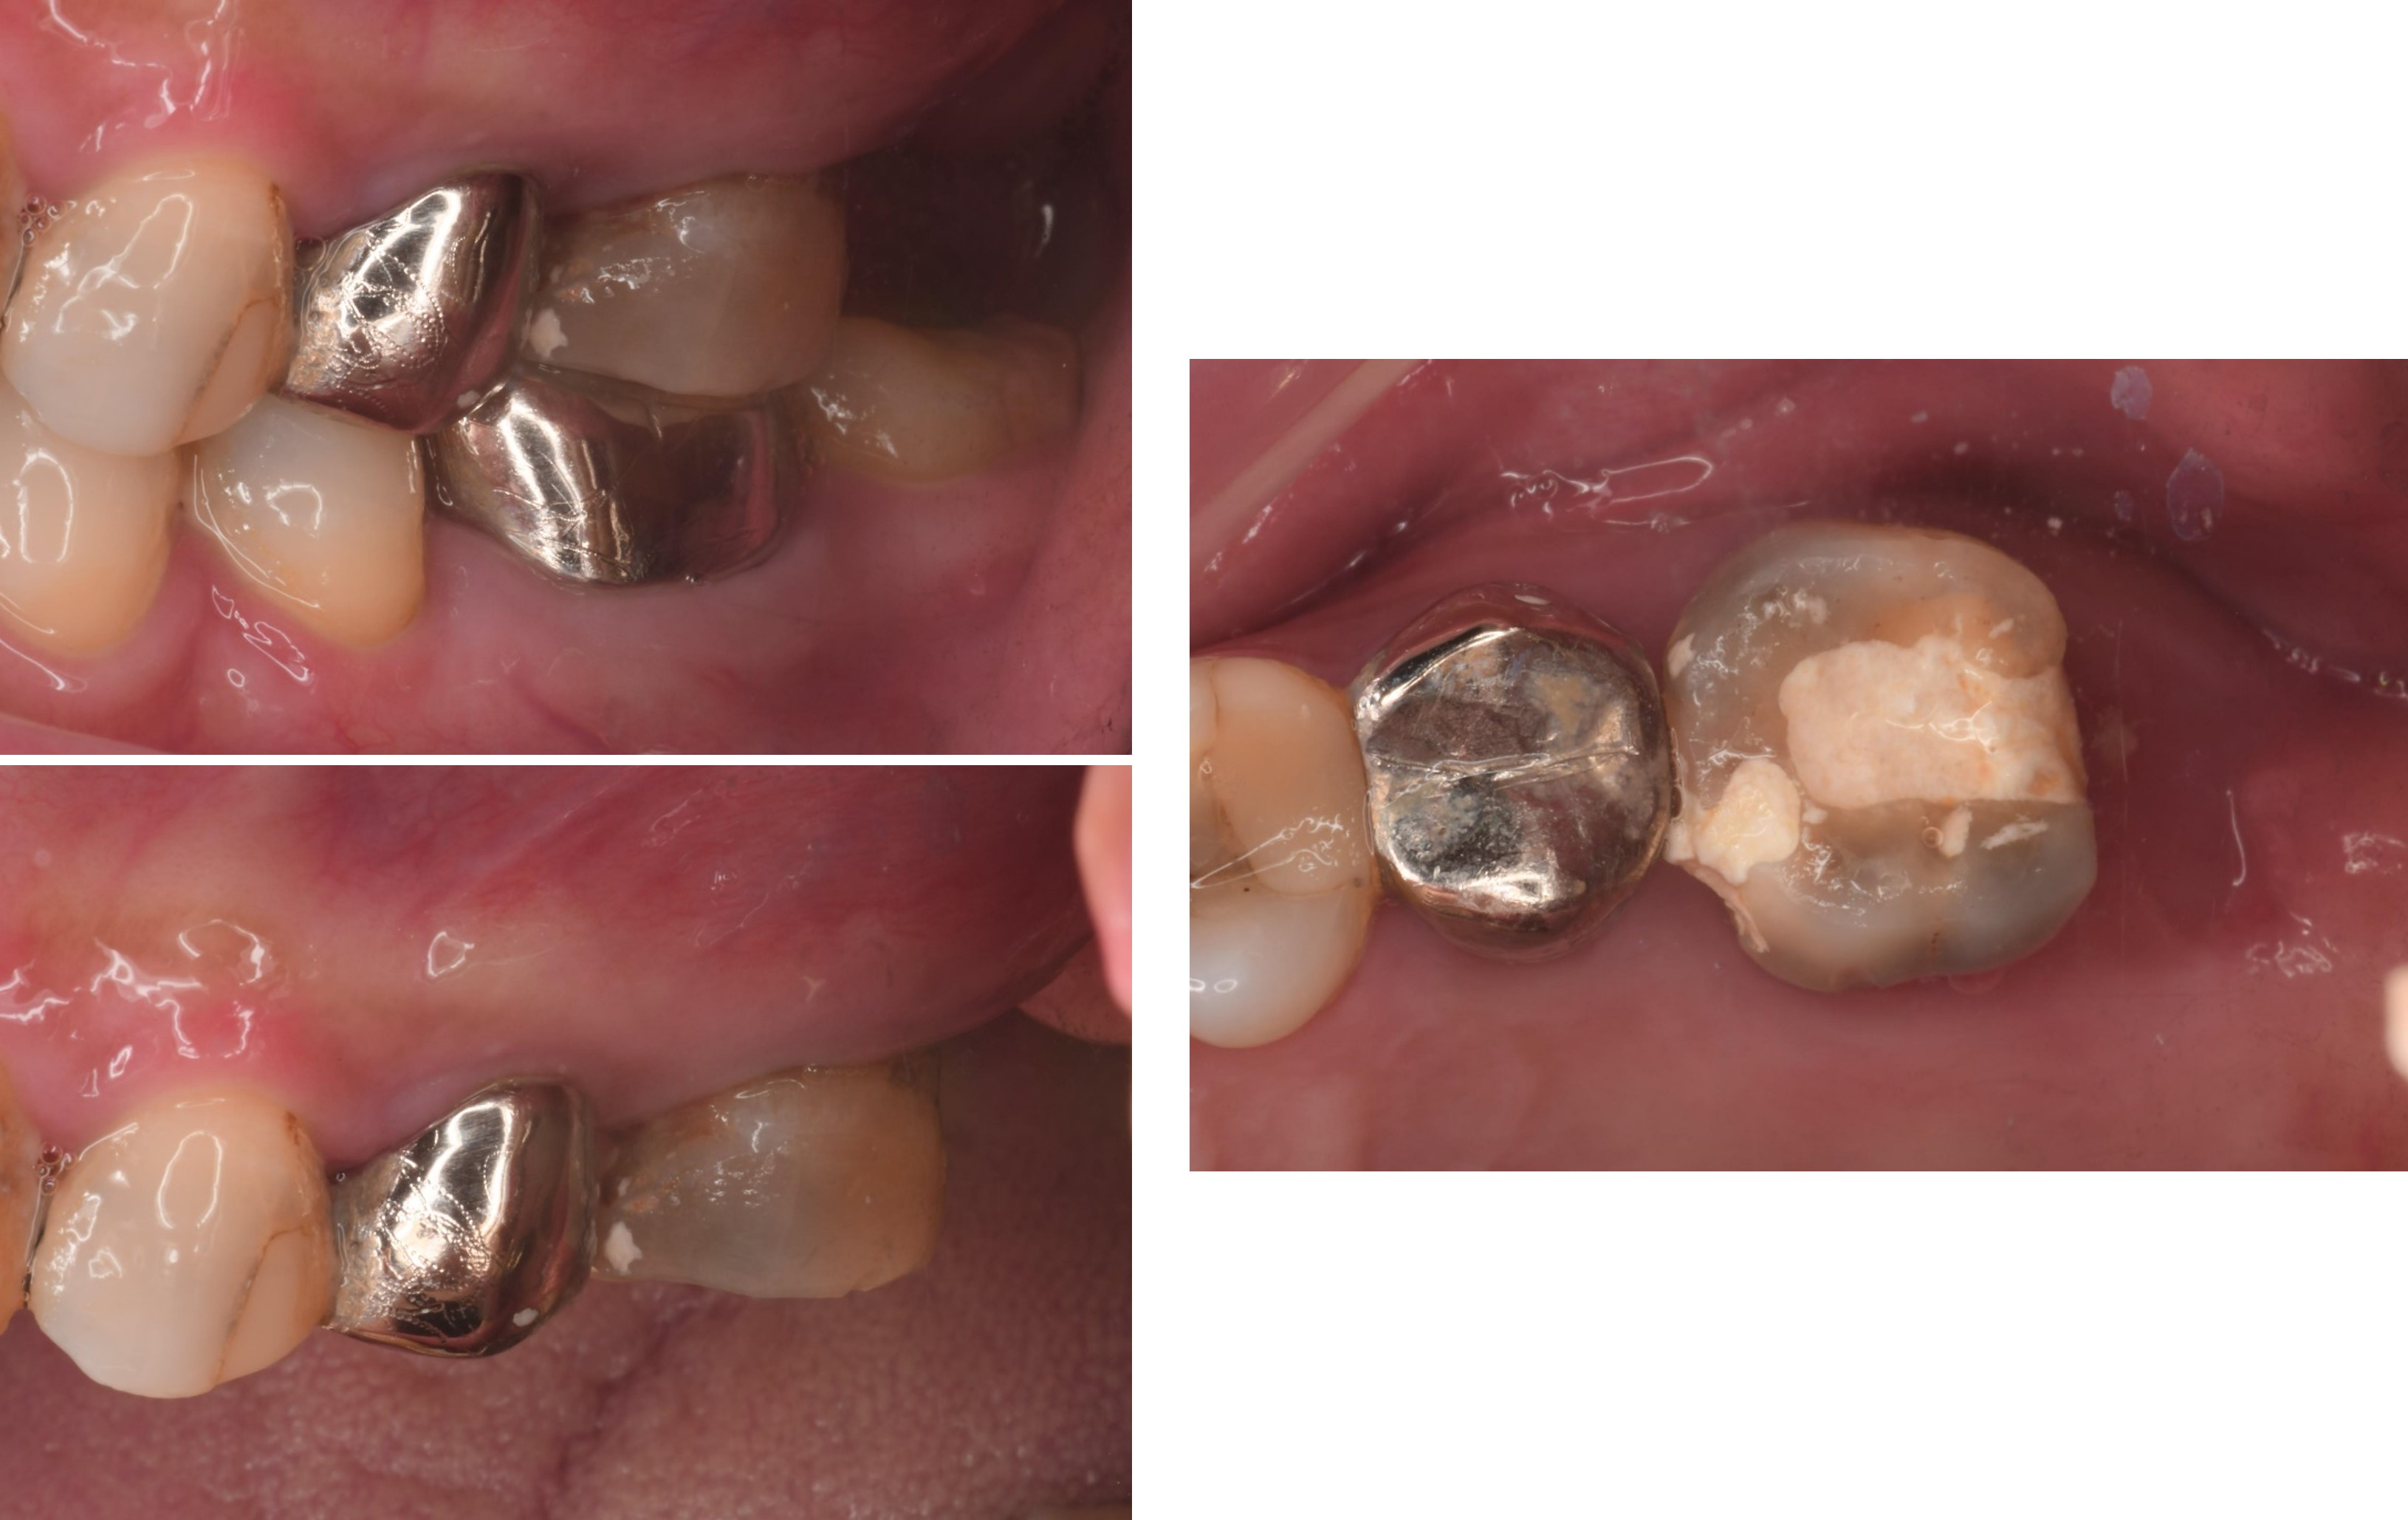

治療前,左上第一大臼齒疼痛

膺復前評估牙齦、牙齒狀態